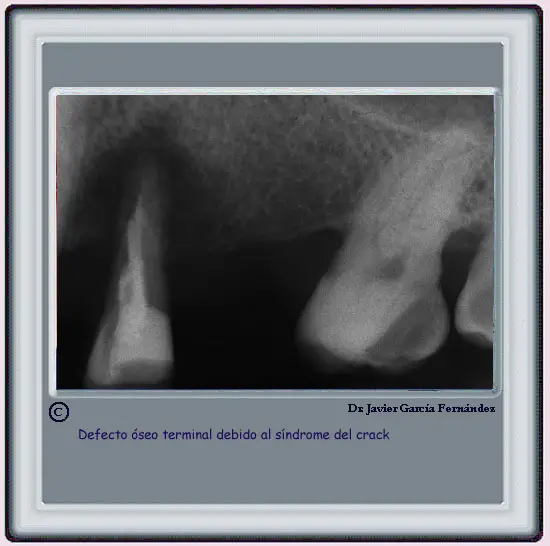

image240